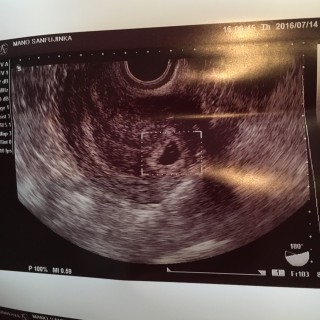

写真:5w3d:mamyyyさん

生理が遅れて3日でドゥーテスト陽性、最終生理からの計算で5週3日の今日、初受診で胎嚢と赤ちゃん、心拍まで確認できました!

赤ちゃんは4.5ミリだと言われました!待望の2人目、どうか無事成長してくれますように...